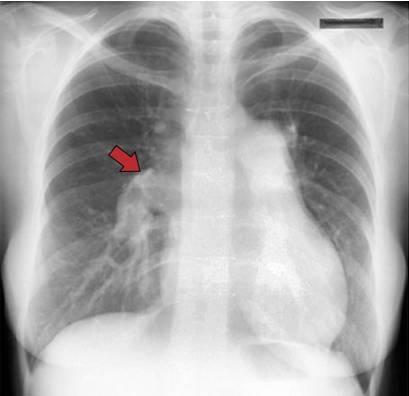

拍胸片第二个月怀孕有伤害吗

拍胸片第二个月怀孕有伤害吗?什么时候才可以拍胸片?需要重新拍胸片?

拍胸片的第二个月怀孕,应休息2周,检查怀孕前13周为重点,怀孕前14周为关键,16周以后为最佳拍期,此时身体尚未发育完全,容易发生贫血,加上胸痛时间较久,如果再继续拍的话,很容易发生意外。

因此,体检前13-16周,准妈妈应停止收检查,放松心情,多休息,要注意饮食调养,注意保暖,预防感冒,也要适当锻炼,不能过度劳累,定期复查。

拍胸片最佳时期是哪个时间段?

一般情况下,在检查胸片前3-7周的时候,孕妇最好休息一周,并且适当休息。如果孕妇因某种原因无法休息,而必须去医院诊治后才能进行相应的诊治。

超声扫描检查建议怀孕第24-28周之间,佩戴X光和磁共振造影的胸片,以免造成胎儿畸形。